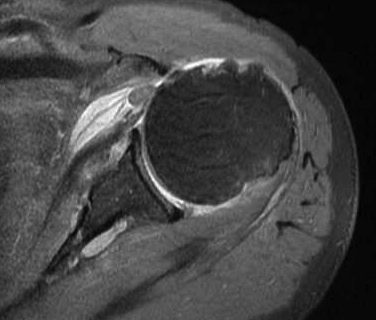

Tendonitis / tendinopathy

Normal

Tendonitis

Tendon thickening / tendinopathy

Sagittal MRI demonstrating severe LHB tendinopathy